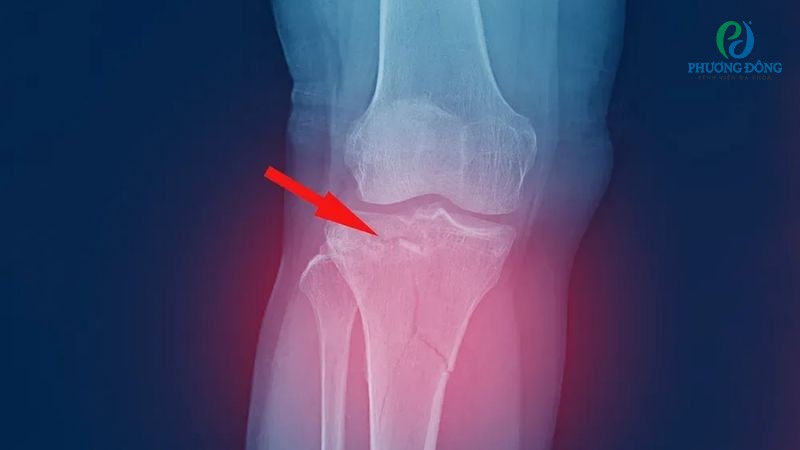

Gãy mâm chày là một dạng chấn thương xương khớp thường gặp, xảy ra do chịu lực tác động mạnh như tai nạn giao thông, ngã từ trên cao xuống hoặc tham gia thể thao. Xét dưới góc độ y khoa, đây là dạng chấn thương nghiêm trọng bởi mâm chày đóng vai trò nâng đỡ trọng lượng cơ thể, duy trì tính ổn định khớp gối.

Đánh giá mức độ nguy hiểm của gãy mâm chày được dựa trên nhiều yếu tố khác nhau. Điển hình bao gồm vị trí gãy, tình trạng di lệch, bệnh lý nền và chấn thương phần mềm kèm theo.

Dù ở mọi trường hợp gãy nhẹ hay nặng, người bệnh không được tiếp nhận chẩn đoán và điều trị đúng cách có thể đối mặt với loạt biến chứng. Nghiêm trọng có thể đề cập tới lệch trục chân, hạn chế vận động, thoái hóa khớp sớm hoặc tàn phế.